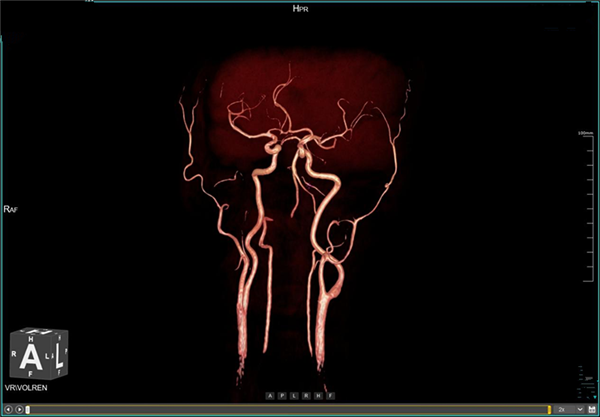

(五)血管成像:无需注射对比剂,对全身血管进行扫描,先进的多角度后处理重建,保证了扫描区域内血管的连续性。用于检查颅内、颈部以及四肢的动脉瘤、动静脉畸形、静脉病变等。

血管成像图